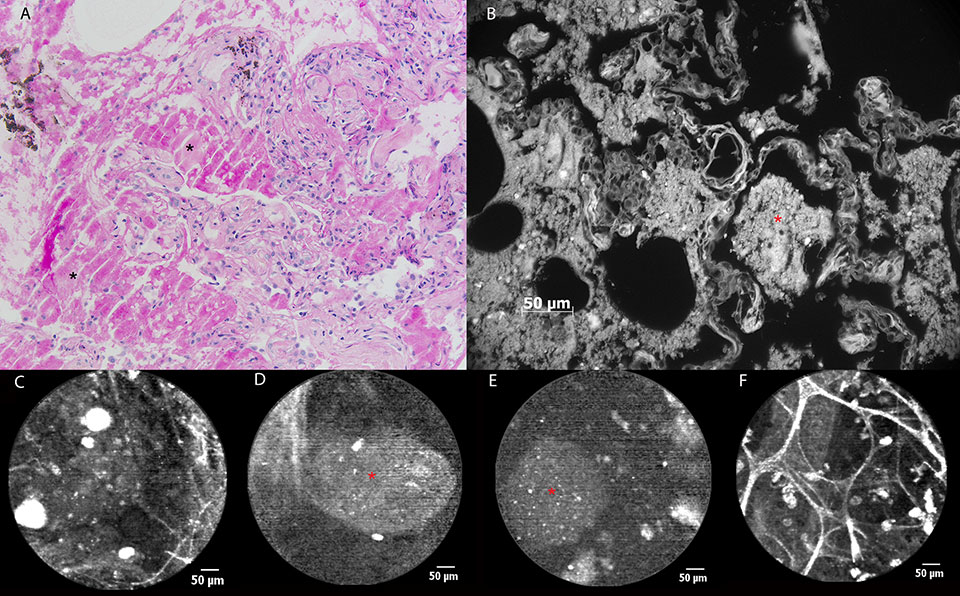

Figure 2

a) Still image of bronchial mucosa during white light bronchoscopy showing ulcerative lesions (arrows) at the level of the left main bronchus. b) pCLE imaging of normal bronchial tissue (blue area) consisting of longitudinally arranged elastic fibres and the orifice of a bronchial gland(asterisk). c) Distortion of the elastic fibre arrangement in areas of diseased mucosa (green area) during pCLE : loss of fibres and fibre disarray. d) pCLE imaging of an ulcer (orange area): complete loss of elastin with the appearance of highly fluorescent cellular structures. e) Histopathological sample showing respiratory mucosa with large areas of squamous metaplasia (asterisk). Local ulceration (centre of image) containing mycelium (encircled area), possibly aspergillus. Inflammatory stromal reaction containing a large number of neutrophils.

A 56-year-old man without striking medical history was admitted to the intensive care unit (ICU) because of bilateral overwhelming pneumonia and sepsis, secondary to an influenza A infection. After 2 weeks of invasive ventilation, flexible bronchoscopy revealed the presence of multiple ulcerative lesions throughout the tracheobronchial tree spreading distally from the main carina (fig. 2a). pCLE imaging showed some areas of normal bronchial mucosa in the left main bronchus (i.e., longitudinally arranged elastic fibres and some orifices corresponding to the presence of bronchial glands [fig. 2b]). Elastic fibre disarray, total loss of elastic fibres, and appearance of redundant thin fibres and zones of denser autofluorescence were noticed in a bronchial ulceration, (fig. 2c). In some frames, fluorescent globular particles could be seen (mean diameter 22 µm), once again of a possible cellular origin (fig. 2d). Bronchial biopsies were taken, confirming the presence of fungal hyphae identified as Aspergillus fumigatus (fig. 2e). Fungal cultures of bronchial tissue were positive for the same infectious agent.

Our experience during the first eighty-eight procedures performed is reflected using these five illustrative cases. The main goal was to give a realistic overview of what the basic technique in pCLE imaging of the respiratory tract is capable of at this moment. As mentioned before, what determines the appearance of central airway mucosa is autofluorescence of elastic fibres. Not surprisingly, in the first two cases pCLE imaging shows the disruption of the normal mucosal lining due to two pathological conditions of the bronchial mucosa (e.g. squamous cell carcinoma and ulcerations due to tracheobronchial aspergillosis). When considering the histopathological specimens, one can easily understand that the layers of elastic fibres located underneath the basal membrane, are disrupted due to the localised ulceration. The pCLE images obtained show that the normal aspect of the bronchial wall is changed, but these images are quite similar in both conditions and can’t be said to be specific for one condition or another.